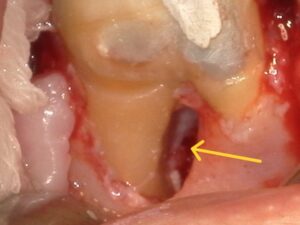

【ストッピングのようなもので仮封してある。遠心側には歯肉ポリープ様のものが見られる】

【黄色矢印 遠心側歯肉ポリープ】

治療方針 まずは痛みを取り除くこと。遠心の壁から歯肉ポリープが見えている状態で根管治療ができるとは考えられないので、髄腔内がどのようになっているのか現状把握して、保存できるかどうかを診断する。

治療経過 近心根、遠心根に入っていたガッタパーチャポイント等を除去し、根管を開放した時点で自発痛が消失。遠心の歯肉ポリープは切除し、隔壁を製作し遠心壁からの唾液侵入を防止。保存できる可能性が出てきたが、根分岐部病変の骨が保存治療だけで再生する可能性は低いので外科的根管治療の説明も行い同意を得られたので、感染根管治療を開始。

【手術中 遠心根の近心側の骨が消失している】

【黄矢印 骨消失】